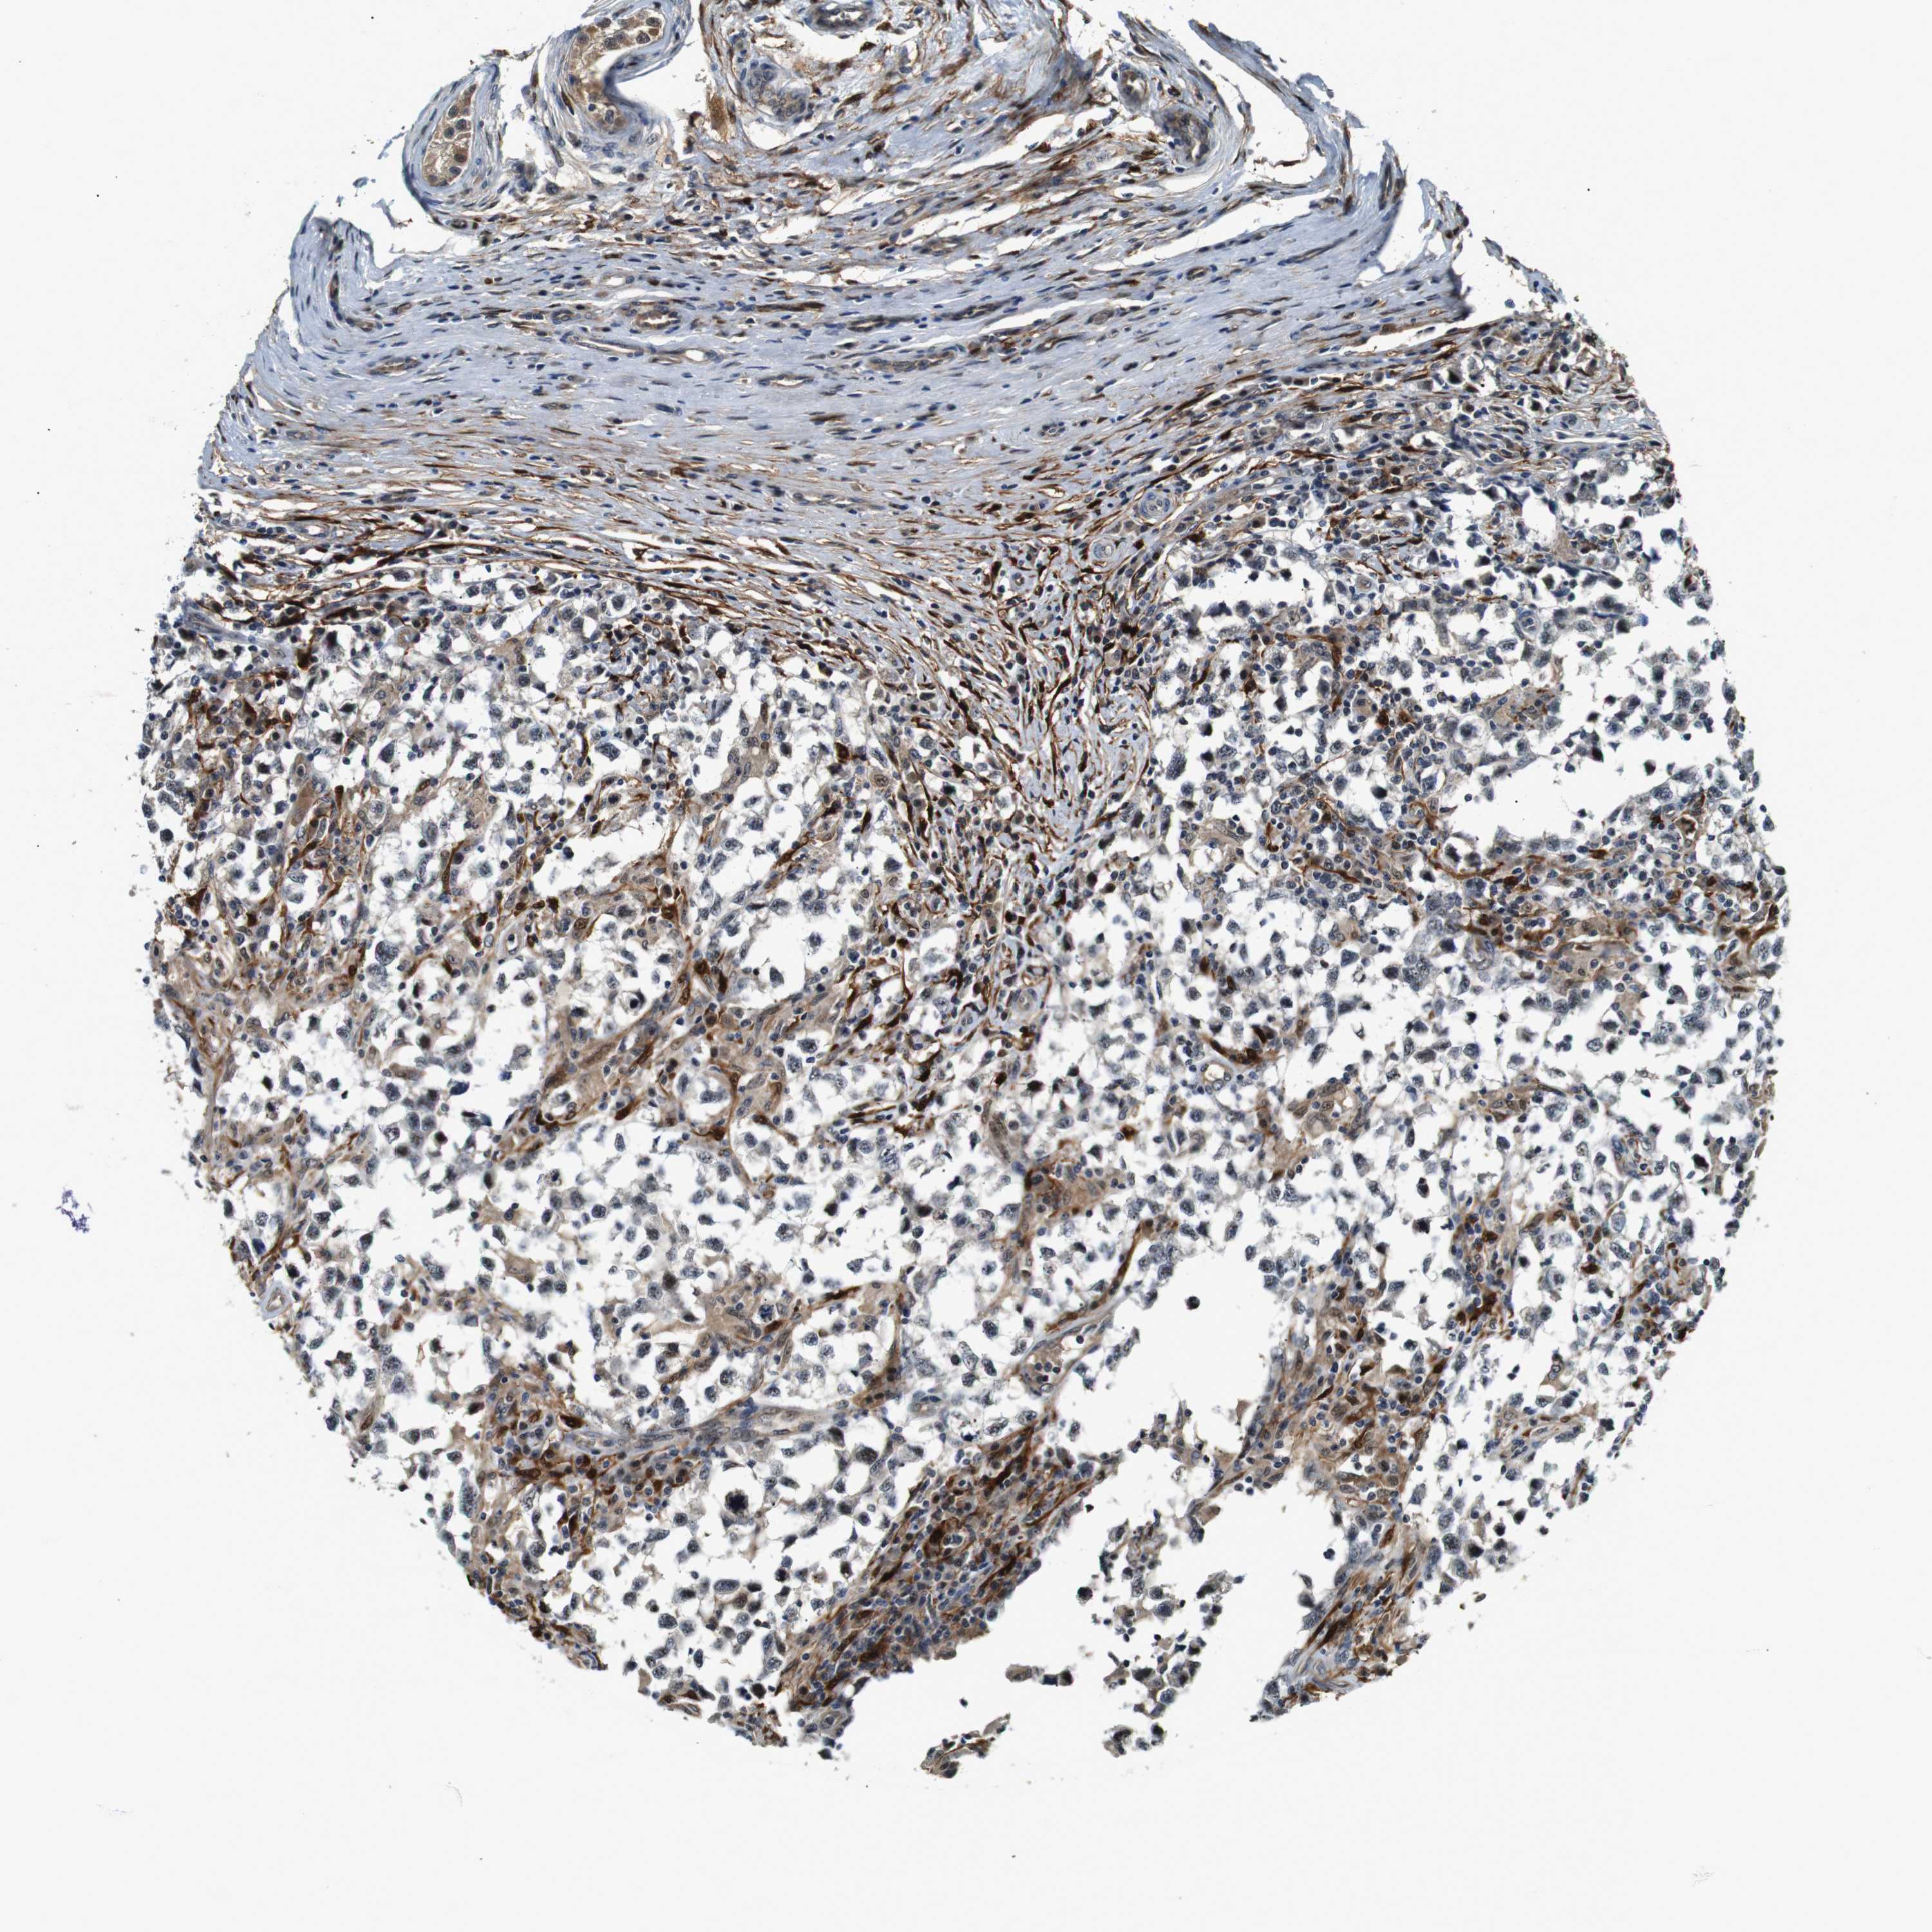

TESTIS CANCER - Protein expressioni

A mouse-over function shows sample information and annotation data. Click on an image to view it in a full screen mode. Samples can be filtered based on level of antibody staining by selecting one or several of the following categories: high, medium, low and not detected. The assay and annotation is described here.

Antibody stainingi

Antibody staining in the annotated cell types in the current human tissue is reported as not detected, low, medium, or high, based on conventional immunohistochemistry profiling in selected tissues. This score is based on the combination of the staining intensity and fraction of stained cells.

Each image is clickable and will lead to virtual microscopy that enables deeper exploration of all samples and also displays staining intensity scores, fraction scores and subcellular localization as well as patient and tissue information for each sample.

Antibody CAB025128

Seminoma, NOS

Carcinoma, Embryonal, NOS